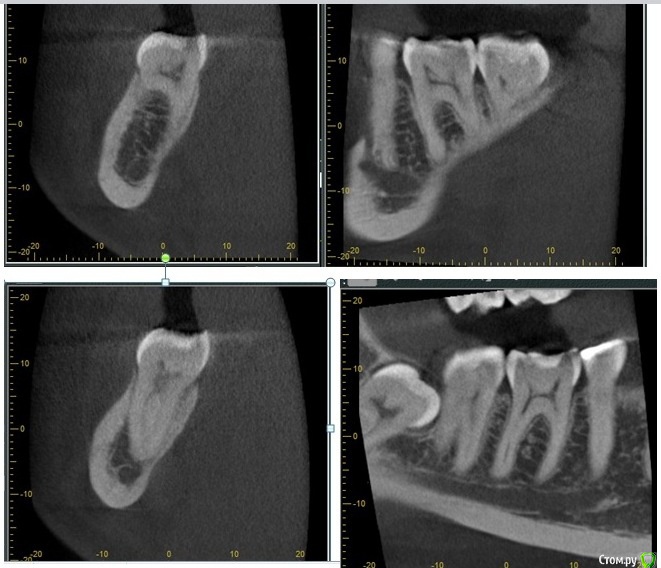

Mashelya Опубликовано 10 мая, 2016 Поделиться Опубликовано 10 мая, 2016 Всем добрый день! Пациентка 27 лет. Санируется. Из анамнеза: нефроптоз, аутоиммунный тириоидит. Лактация.17 апреля меняли пломбу с дефектом на 46, 47. Жалоб на боль не было. Пломба не большая, кариес под пломбой средний, не критичный по глубине. И вот она записалась 3го мая с жалобами на боль на накусывание в зубе 46. Первая мысль- завышает пломба, но нет, завышение не выявлено и после пришлифовки изменений не было. Перкуссия слабо + (по словам пациентки не больно, но отличается от соседних зубов). При зондировании на жев. поверхности обнаружена точка, где нажатие зондом вызывает боль. Далее подумала, что могла пересушить дентин. Убрала пломбу под анестезией и на неделю закрыла временной- септопак, чтобы посмотреть динамику. Отправила на клкт на всякий случай. На снимке не вижу ничего необычного. Жалоба на кусание остается даже с временной пломбой. С чем может быть связано и какая тактика? Ссылка на комментарий

Саидчон Опубликовано 10 мая, 2016 Поделиться Опубликовано 10 мая, 2016 (изменено) Маргинальный периодонтит 46 Изменено 10 мая, 2016 пользователем Саидчон Ссылка на комментарий

Vladimirov Опубликовано 11 мая, 2016 Поделиться Опубликовано 11 мая, 2016 Маргинальный периодонтит 46 Ссылка на комментарий